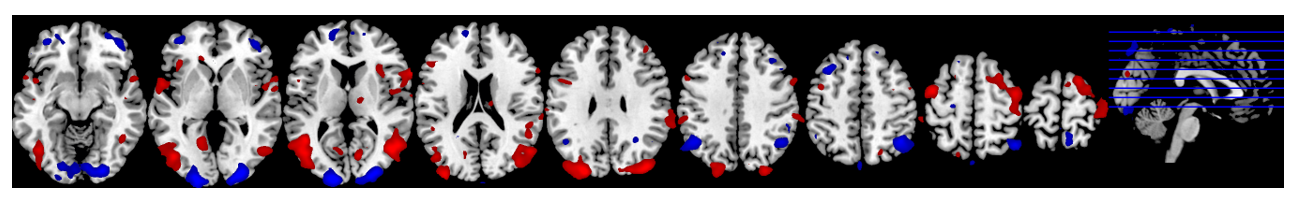

Door de verkoopaantallen te koppelen aan de bijbehorende breindata, werd er door onze wetenschappers op basis van de neurale netwerken van succesvolle of juist falende kledingstukken een voorspelmodel gebouwd. Zo bleken gebieden die te maken hebben met visuele verwerking belangrijk, maar ook de beloningsgebieden en een gebied dat betrokken is bij sociale interactie.

Het neurale netwerk van goed verkopende kleding

De resultaten laten echter nóg iets bijzonders zien: De wetenschappers van Neurensics voorspellen slecht verkopende kledingstukken twee keer zo goed als goed verkopende kledingstukken. We vroegen ons af hoe dat komt, totdat we de breinfoto’s zagen die dat lijken te verklaren.

De neurale patronen van de beter verkopende kledingstukken, laten een belangrijk verschil zien met de kleding die slecht verkoopt. Het zijn met name de gebieden die te maken hebben met sociale relevantie. Het lijkt erop dat we een kledingstuk dat we niet zien zitten in één keer mentaal hebben afgewezen. Een kledingstuk echter dat we wél zien zitten, wordt nog eens een tweede keer overwogen: “wat zullen anderen ervan vinden?”. De sociale overweging speelt een belangrijke rol die logischerwijs niet van toepassing is op kleding die we toch al hebben afgewezen.